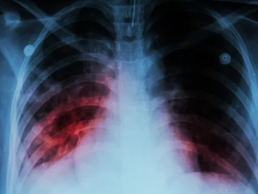

Diretrizes atualizadas para tratamento da tuberculose reduzem duração de regimes terapêuticos

Uma nova diretriz de prática clínica emitida pela American Thoracic Society, publicada na edição de janeiro do American Journal of...